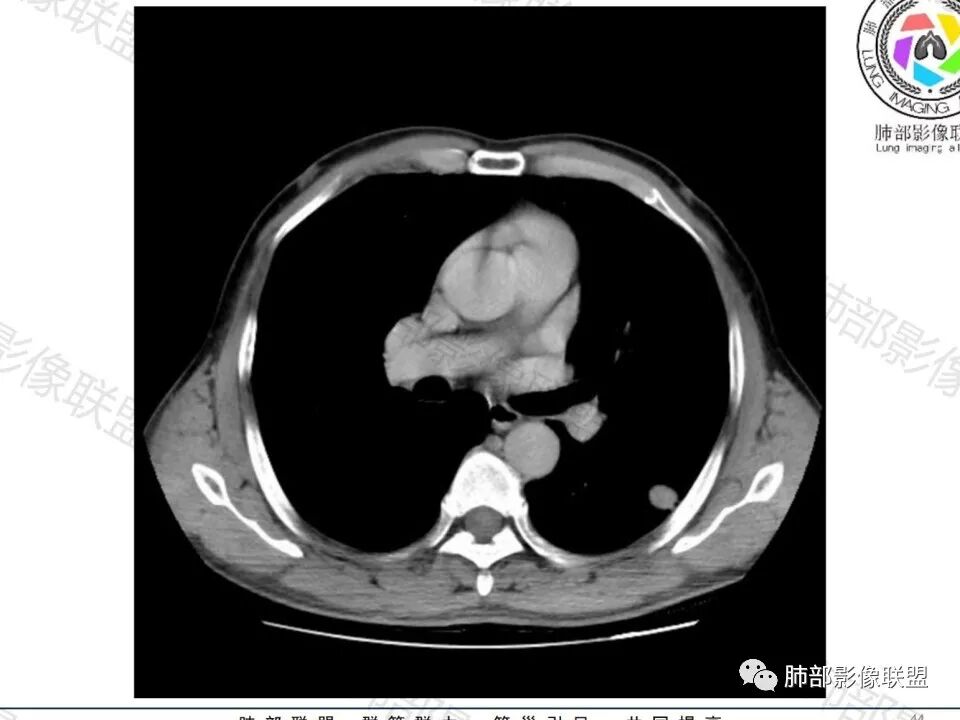

这枚结节的纵隔窗在没有调节窗位的情况下,已经很密实了,说明这个结节里面是软组织的成分,这与普通炎性结节(隐球菌等)的密度还是有区别的,很多年前就有人提出,纵隔窗显示越大,恶性可能越大;

结节周围有磨玻璃影,边界似清不清的,但是总体不如炎性晕征那么模糊;

增强的程度很难讲,但是不均匀强化是可以确定的;

有收缩力,但是很轻,按照常理,实性结节因为有占位效应,不太会有收缩力,但是叶间胸膜有凹陷。所以讲,这个结节还是开了放心。